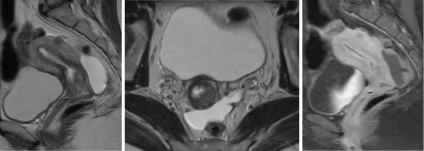

RMN-ul a imaginii abdomenului

RMN-ul este o valoare de diagnostic in perioada preoperatorie cu interventii chirurgicale conservare a sânului. Este de asemenea posibil tomografia exploatație, în scopul de a clarifica diagnosticul cu date incorecte cu ultrasunete. utilizat în mod avantajos tomogram ponderat T1 pe care fibrom este definită ca formarea unei contururi netede clare, cu o intensitate a semnalului moderat scăzută. Când procesul de lungă durată, apariția unor focare de necroză și calcificare în interiorul tumorii. In tomogram, se pare ca formarea de mare intensitate neuniformă în structură, cu bordura o intensitate mai mică.

RMN-ul a bazinului. endometrioza. Uterul este extinsă și corespunde 7-8 săptămâni de sarcină (dar pacientul nu este gravidă, doar atât de mult o consecință a uterului în endometrioza). Multiple de comutare indicată de săgeată.

Adenomioza. chist endometrioide pe stânga. Exterior heterotopie endometrioid din stânga (secțiuni axiale. Imagine ponderată T2 și o imagine ponderată T1).

Cancerul de col uterin, Ib pas. Volumul determinat formarea de col uterin, fără semne de infecție în grăsime parametrial înconjurat perimetral stromă. La scanarea postkontrastnom (imaginea din stânga) este determinată de țesut tumoral mai puțin intensă acumulare HF, comparativ cu țesuturile nemodificate ale uterului.

Imaginea prezinta RMN-ul este indicat prin săgeți de dezvoltare anomalie a uterului cu două coarne